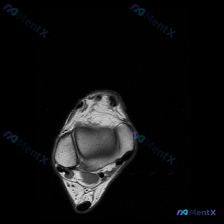

看到一个挺有代表性的读片问题,整理一下完整的分析思路分享给大家。 病例基础信息 这是一份单张踝关节MRI T2序列轴位图像,临床疑问是观察到「软组织积液」,需要解读。 影像结构完整评估 我们先把影像上能看到的结构逐一梳理清楚: 1. 骨骼结构:可见胫腓骨远端截面,骨皮质轮廓清晰,骨髓信号没有异常高信...